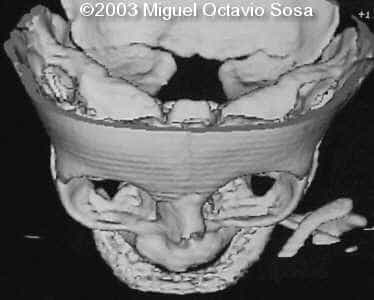

19-year-old primigravida. During third week of pregnancy, she is vaccinated with anti-measles vaccine, without knowing about the pregnancy. There are no important details before the pregnancy. These are images of the face of the fetus. Pay specific attention to the midface.

19-year-old primigravida. During third week of pregnancy, she is vaccinated with anti-measles vaccine, without knowing about the pregnancy. There are no important details before the pregnancy. At 22nd week, an ultrasound is performed demonstrating a single nasal channel on the left side and absence of right nostril.

A female newborn was delivered at 38 week, by cesarean section due to breech presentation. Size of right eye is bigger than left, and there is total absence of the right nostril. Apgar 9 at birth. No complications during postpartum. Newborn is actually under study by plastic surgeon.

These are the 3D CT reconstruction.